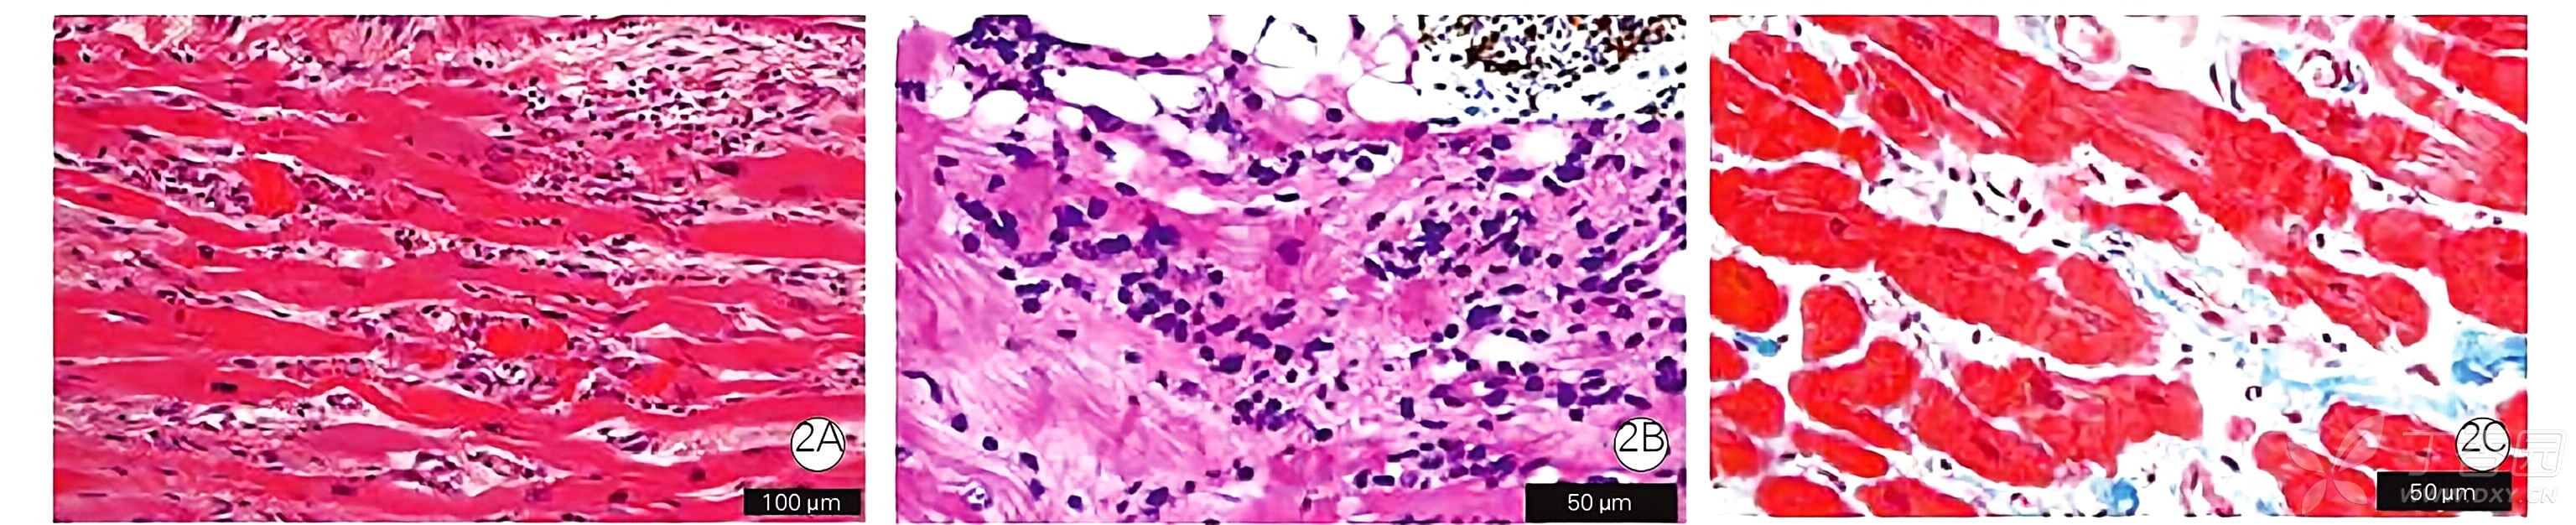

myocarditis

| 急性心肌炎 | 发病后<30 天的心肌炎,组织学上以炎症细胞浸润和心肌细胞损伤为特征(变性/坏死伴有炎症细胞在心肌细胞周边的侵袭)。 当心肌活检不可行时,除临床病程和症状提示心肌炎外,还可获得以下结果,即可临床诊断为急性心肌炎。 (1)血液中高敏心肌肌钙蛋白水平升高 (2)心脏 MRI 上提示水肿的发现 | + | + |

慢性活动性心肌炎 | 发病后≥30 天的心肌炎,组织学上以炎症细胞浸润和心肌细胞损伤为特征(变性/坏死伴有炎症细胞在心肌细胞周边的侵袭)。 即使在组织病理学上没有看到心肌细胞的损伤,出现以下任何一种结果都表明有可能是临床慢性活动性心肌炎: (1)血液中高敏心肌肌钙蛋白水平持续升高 (2)心肌组织中的 CD3+ T 细胞≥24/mm2(5.8 细胞/HPF) (3)心肌组织中的 Tenascin C(4C8)染色阳性发现。 | + | + |

| 慢性心肌炎 | 发病后≥30 天的心肌炎,组织学上以炎症细胞浸润为特征,但无心肌细胞损伤(变性/坏死伴有炎症细胞在心肌细胞周边的侵袭)。 这可能是介于急性心肌炎和慢性心肌炎之间的一个过渡阶段。 | + | - |

| 慢性炎症性心肌炎 | 发病后心肌炎症持续≥30 天,伴有心室壁运动下降。 组织学上,有纤维化伴随心肌细胞的异常(心肌细胞大小的变化等)和炎症细胞的浸润(心肌组织中的白细胞≥14/mm2,CD3+T 细胞≥7/mm2)。没有心肌细胞损伤(变性/坏死伴有侵袭的心肌细胞周边的炎症细胞)。 | + | - |